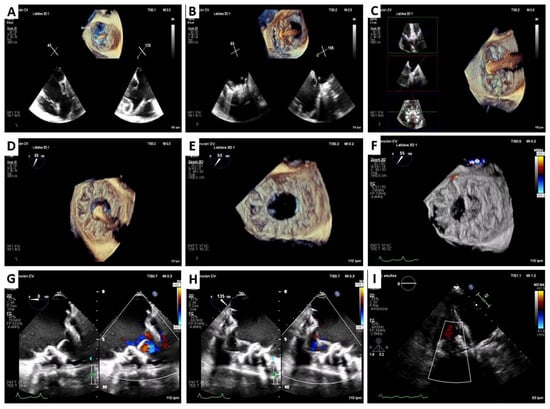

2. Cardiovalve Cases